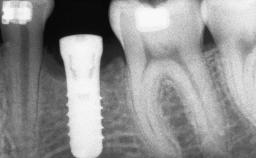

A 20-year-old woman was referred for implant therapy in 2004. Her medical history revealed no significant findings, and neither did she smoke nor take any medications. An extraoral examination revealed no abnormalities of the skin, hair or nails. The intraoral examination revealed only 11 permanent teeth clinically. These were normal in shape, size, and color. In addition, eight retained deciduous teeth (53, 62, 63, 71, 72, 73, 81, 82) were present. No abnormalities were detected during the general examination. The family history revealed that the patient’s father and two sisters were on record with similar conditions. The clinical examination revealed a thick gingival biotype. No recession of the attached gingiva was noted, but the retained deciduous teeth were mobile and unsightly. As a syndrome had not been diagnosed, the case was categorized as non-syndromic oligodontia.

# of Implants 12

Type of Implants One-Piece|Reduced-Diameter

Bone Augmentation Horizontal|Staged

Augmentation Materials Autogenous chips|Autogenous block(s)|Membrane

Bone Volume Deficient horizontally, requiring prior grafting